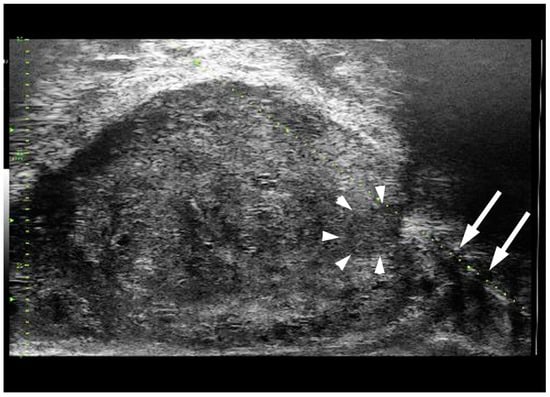

- Cornud, F.; Lefevre, A.; Flam, T.; Dumonceau, O.; Galiano, M.; Soyer, P.; Camparo, P.; Barral, M. MRI-directed high-frequency (29MhZ) TRUS-guided biopsies: Initial results of a single-center study. Eur. Radiol. 2020, 30, 4838–4846. [Google Scholar] [CrossRef]

- Ghai, S.; Eure, G.; Fradet, V.; Hyndman, M.E.; McGrath, T.; Wodlinger, B.; Pavlovich, C.P. Assessing Cancer Risk on Novel 29 MHz Micro-Ultrasound Images of the Prostate: Creation of the Micro-Ultrasound Protocol for Prostate Risk Identification. J. Urol. 2016, 196, 562–569. [Google Scholar] [CrossRef] [PubMed]